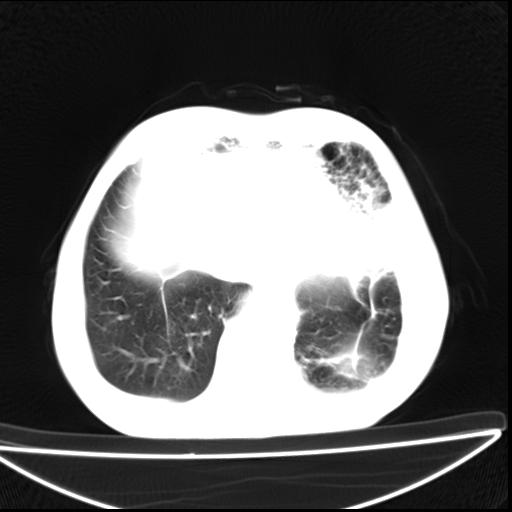

男  70岁,发烧咳嗽4天。盗汗,消瘦。无痰中带血丝,以前有肺tb病史,ct见,双肺tb,左侧胸廓塌陷,左胸膜肥厚粘连。纵隔移位,右侧胸腔积液,大家说说那个心影前左肺舌叶除了肺大炮还有炎症还是干酪性肺炎?有占位吗?我看纵隔淋巴结也大。

1)两肺继发性肺结核并左肺上叶肺不张,支气管扩张。2)双侧胸膜炎(胸膜增厚+少量胸腔积液)。

两肺继发性肺结核并感染,左肺上叶肺不张。建议ct增强。